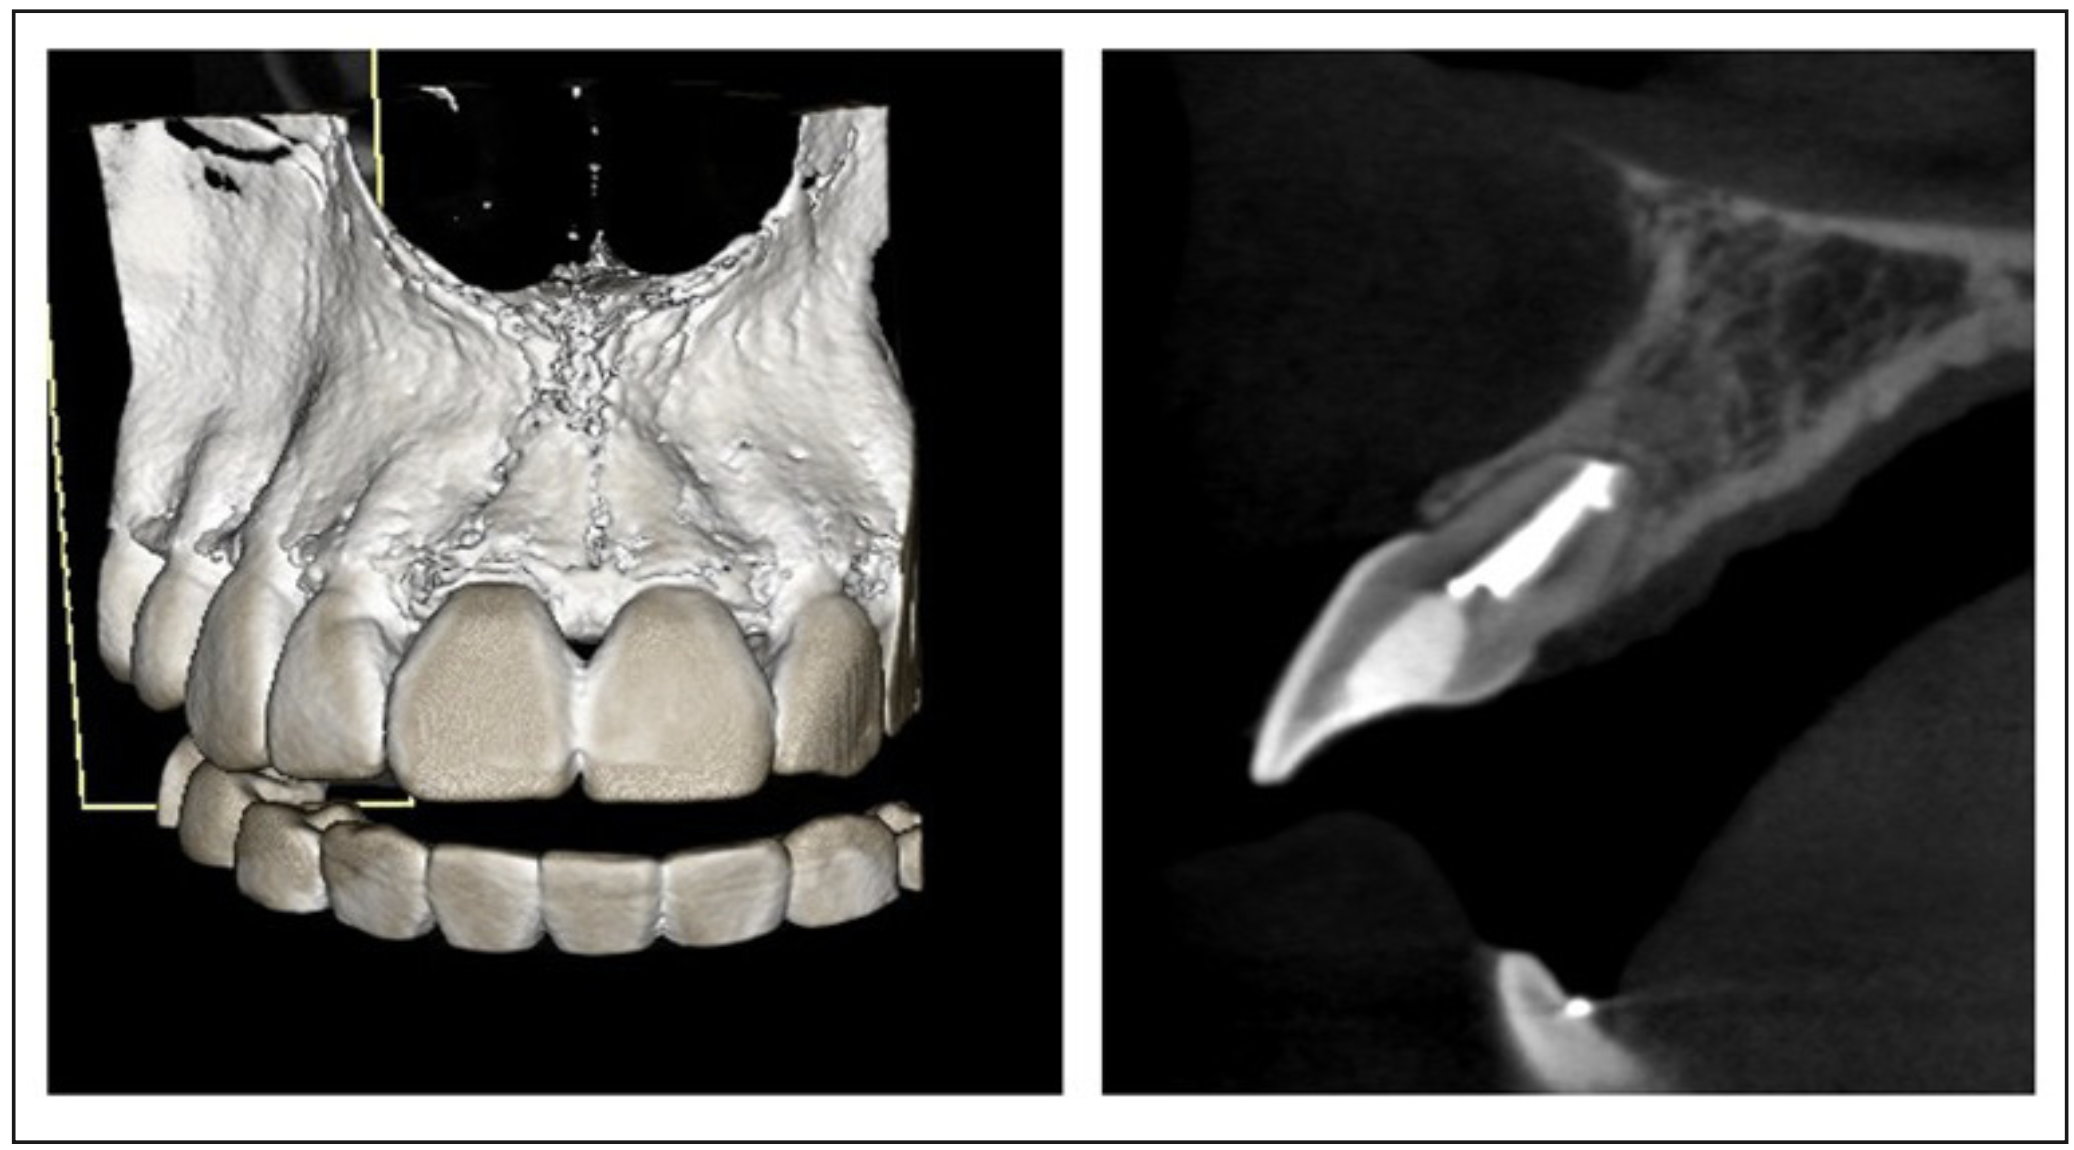

En el examen radiológico se observa una lesión osteolítica apical circunscrita de tamaño 5x8 mm. (Figura 1); además, se decidió complementar con tomografía computarizada de haz cónico debido a la movilidad presentada (Figura 2) en la que se logró visualizar la lesión en forma más precisa entregando una medida de aproximadamente 5x8,5x5mm, con compromiso de la tabla ósea vestibular, manteniendo una banda de tejido óseo a nivel cervical vestibular de entre 3,51 a 4,36 mm y mantención de la tabla palatina.

Figura 2. Tomografía computarizada de haz cónico del diente 1.1. Restauración coronaria penetrante. Canal radicular amplio con importantes signos de remodelado apical. Se observa lesión osteolítica periapical con límites netos, aparentemente corticalizada, cuyos diámetros mayores alcanzan 5,06x8,55x5,07mm. Adelgazamiento de la tabla vestibular. Trabeculado óseo heterogéneo.

Posteriormente, se controló a los 3, 6 y 12 meses observando una excelente evolución en el tiempo: ausencia de signos o síntomas compatibles con inflamación o infección tanto clínica como radiográficamente, siendo la ausencia de movilidad uno de los factores de bienestar más importantes para la paciente. En la tomografía de haz cónico del control anual observamos la recuperación de la tabla vestibular y el relleno óseo del defecto observado anteriormente (Figura 6 y 7).

Figura 7. Tomografía de haz cónico de evolución al año post microcirugía. Se observa el relleno hiperdenso de la obturación endodóntica con signos de remodelación apical, trabeculado óseo perirradicular conservado. Tablas óseas vestibular y palatinas conservadas, con mínima interrupción de la tabla ósea vestibular.